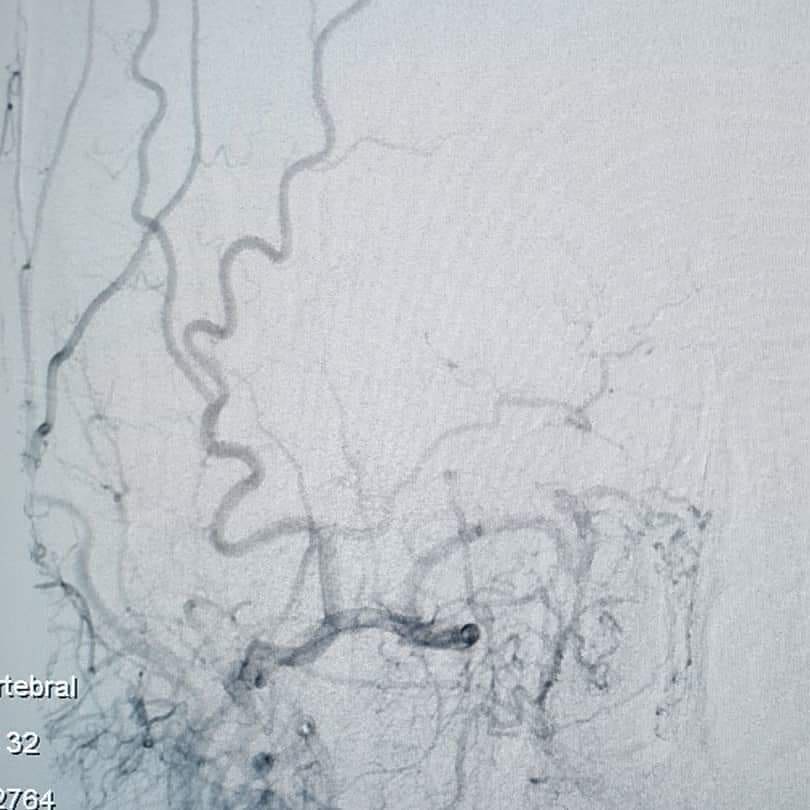

Akut Total İCA okluzyonu olan hastada aspirasyonu ve stent trombektomi ile tam açılma sağlandı. İşlemden sonra hastanın nörolojik bulguları geriledi ve 1 hafta sonra taburcu oldu. #radyoloji #tıbbigörüntüleme